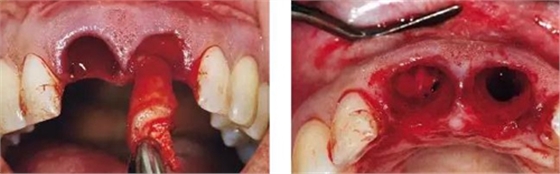

圖6、前庭溝半圓形切口,翻瓣后暴露左側(cè)和右側(cè)的骨缺損。

圖7、去除了肉芽組織和根尖感染組織,仔細沖洗后,可見雙側(cè)拔牙窩唇側(cè)骨壁有大面積缺損。

圖8、植入2顆Camlog平行壁螺紋種植體,扭矩達35Ncm。安放兩個粗直徑的愈合帽,防止軟組織退縮和凹陷。